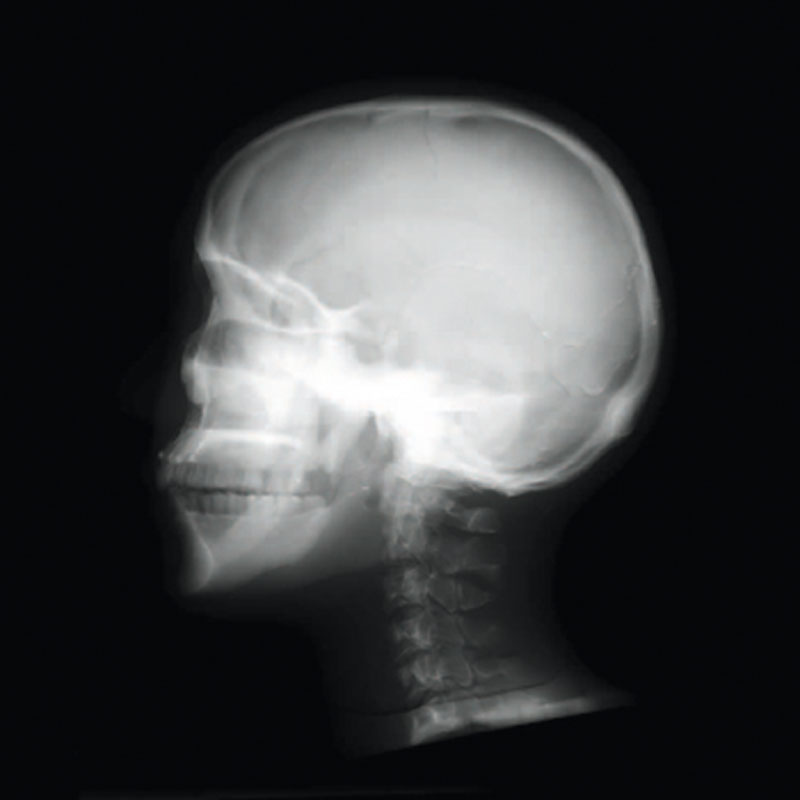

Ein einzigartiges Ganzkörperphantom für CT bietet eine Vielzahl von Ausbildungs- und Forschungsmöglichkeiten. Das Phantom kann auch für normales Röntgen benutzt werden und gibt lebensnahe Bilder. Es benden sich keine Metallteile oder Flüssigkeiten im Phantom. Die wichtigen Gelenke haben eine menschenähnliche Beweglichkeit und erlauben vielfältige Positionen für die Übung. Das Phantom kann in 10 Teile zerlegt werden. Die verbesserten Schultergelenke erlauben es, die Arme nach oben zu bewegen. Die künstlichen Organe sind anatomisch korrekt und haben entsprechende HU-Zahlen.

- Synthetischer Schädel

- Halswirbel

Radiologische Absorption und Hounsfield-Nummer ähnlich dem menschlichen Körper.